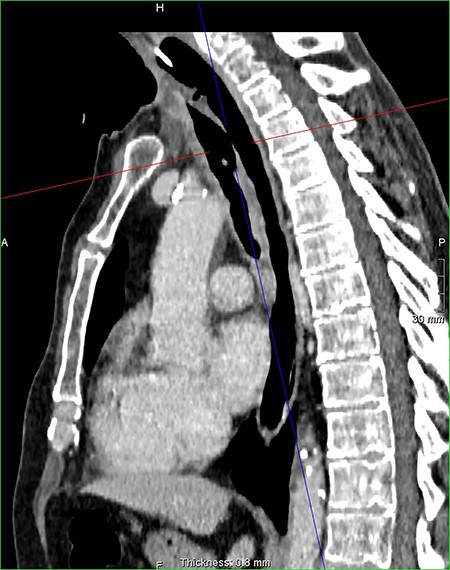

On examination, the patient had no obvious abnormality in the valve puncture. The stoma site was normal except for some crusting around the edges. A marked abnormality on the tracheal wall ~6 cm inferior to the stoma site was revealed, through a flexible nasal endoscopic examination. The abnormality was later confirmed to be a TOF. The patient underwent a computed tomography (CT) scan to delineate the surrounding anatomy as to facilitate the planning of the surgery (Figs 2–4).

Axial reconstruction post contrast CT neck and thorax images with 4 mm defect/tracheoesophageal fistula located 8–9 cm from tracheostomy level and 12 cm proximal to the carina.